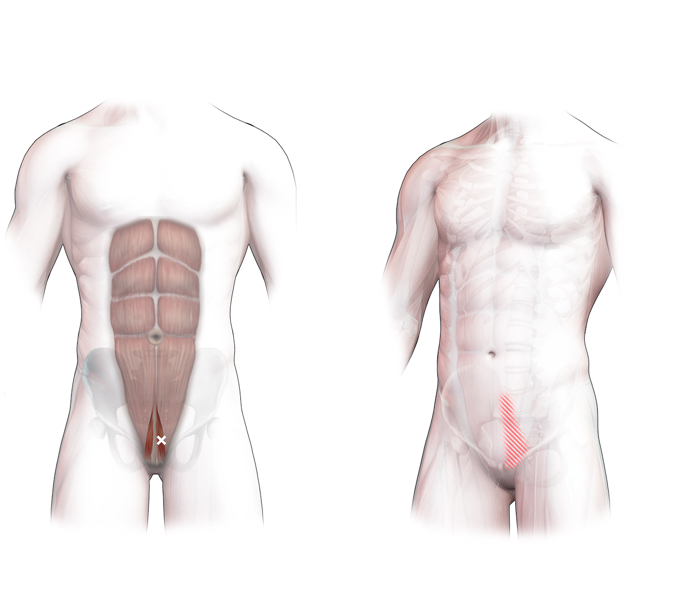

Spieren (Nederlands)

Spieren (nederlands)

Spieren (Latijn)

Spieren (latijn)